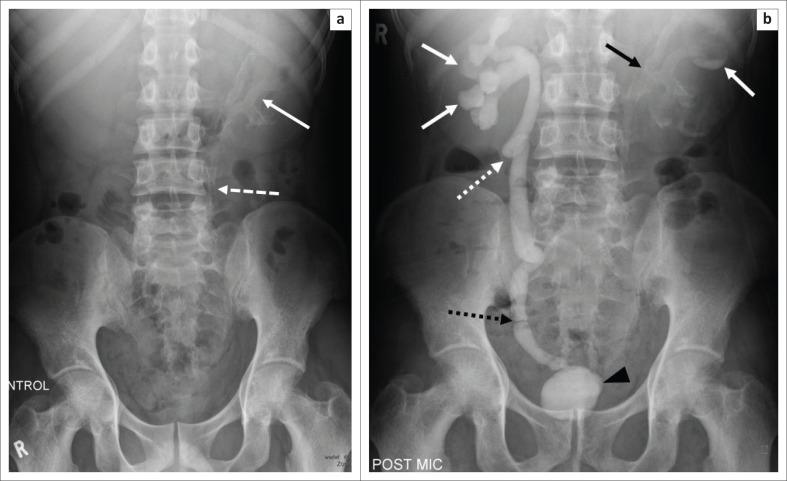

Extra-pulmonary tuberculosis (EPTB), caused by , is the leading cause of communicable disease-related deaths in people with human immunodeficiency virus (HIV) worldwide and in South Africa. disseminates haematogenously from an active primary lung focus and may affect extra-pulmonary sites in up to 15% of patients. Extra-pulmonary TB may present with a normal chest radiograph, which often causes a significant diagnostic dilemma. This review describes the main sites of involvement in EPTB, which is illustrated by local imaging examples.

由……引起的肺外结核病(EPTB)是全球和南非人类免疫缺陷病毒(HIV)感染者中与传染病相关死亡的主要原因。……从活跃的原发性肺部病灶经血行播散,高达15%的患者可能累及肺外部位。肺外结核病可能胸部X线片表现正常,这常常造成重大的诊断困境。本综述描述了肺外结核病的主要受累部位,并通过局部影像学实例进行说明。 (注:原文中“caused by ”和“disseminates haematogenously from an active primary lung focus and may affect extra-pulmonary sites in up to 15% of patients.”前缺失关键信息)